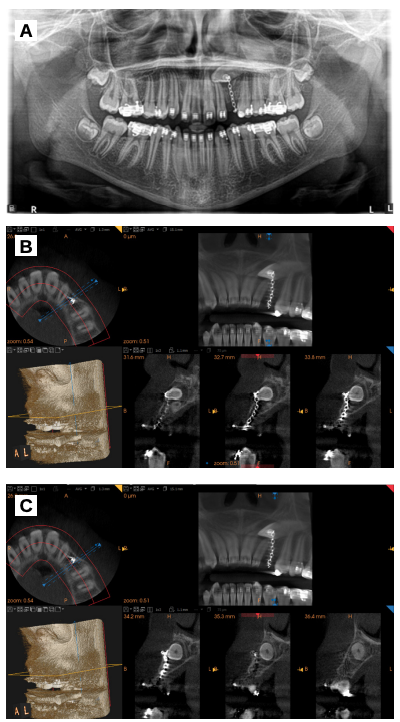

Se realizaron mediciones con el CBCT para determinar las dimensiones exactas del canino y de la zona receptora para asegurar que el espacio era correcto y no era necesario modificarlo con ortodoncia. Así mismo, se evaluaron las relaciones anatómicas con estructuras adyacentes para evitar posibles complicaciones durante la cirugía (Figura 1).

colocó un botón de ortodoncia para intentar traccionar del canino,

sin éxito. B, C. Cortes CBCT previos a la cirugía.